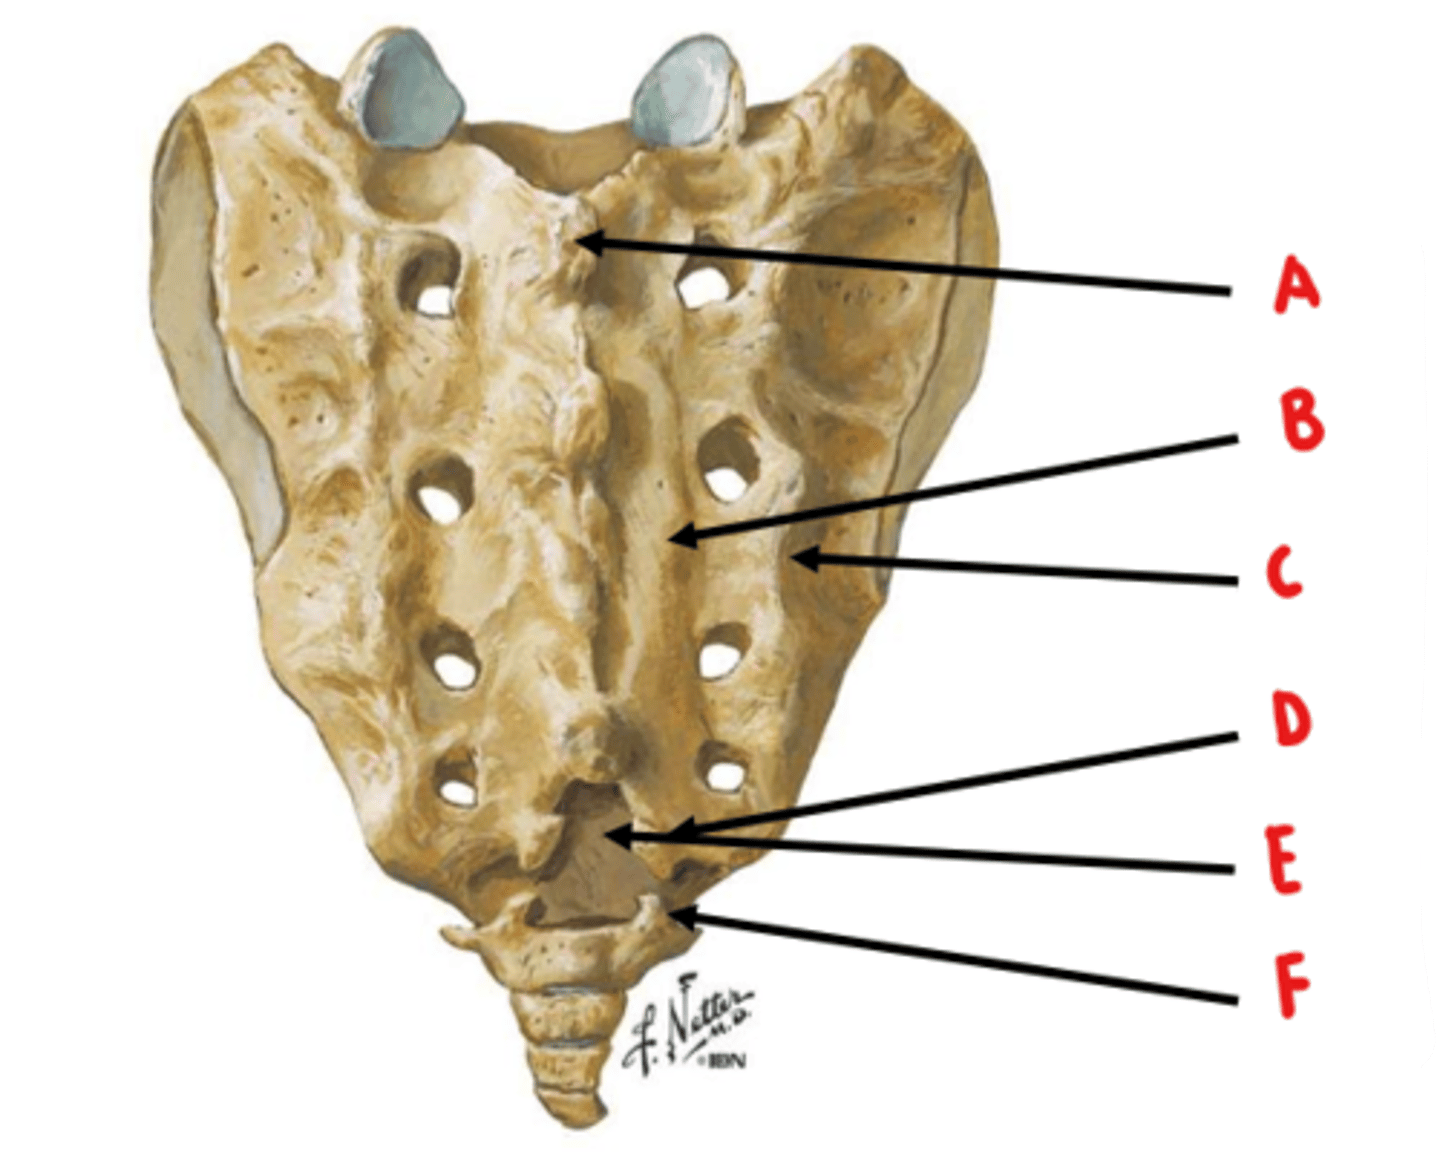

median sacral crest

Identify A

medial sacral crest

Identify B

lateral sacral crest

Identify C

sacral cornua

Identify D

sacral hiatus

Identify E

coccygeal cornua

Identify F

anterior sacral foramen = ventral rami

posterior sacral foramen = dorsal rami

ventral rami are larger because they innervate a larger area of tissue

What structures exit through the anterior and posterior sacral foramen? Which is larger and why?